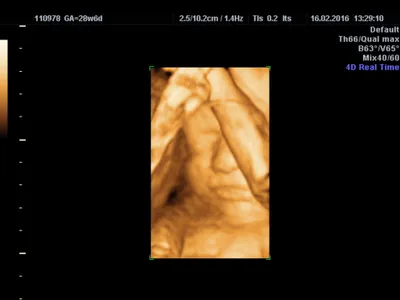

4DのDはディメンション(dimension)の頭文字で、4Dエコーは4次元エコーという意味です。縦、横、高さの3次元(3D)の立体情報に加えて、動きという時間の要素が加わるので、4次元(4D)ということになります。

4Dエコーでは、おなかの赤ちゃんの体が立体的に、動いている様子をリアルタイムで

見ることができます。

ただし4Dエコーでは、見たい場所の前が空いていないと、きれいな画像は得られません。例えば、おなかの赤ちゃんの顔の前に手があれば顔は見えなくなります。胎盤や子宮の壁が非常に近い場合や羊水が少ない場合などでも、うまく見ることができません。

しかし、赤ちゃんの向きがちょうどよく、見た場所の前が空いているなど条件が合えば、あくびや指しゃぶり、表情の変化なども見ることができます。

3Dエコーは4Dエコーと同様に、おなかの赤ちゃんを立体的に描き出します。

3Dエコーは静止画(縦、横、高さの情報)で動きがありませんが、これに動き(時間の情報)が加わったのが4Dエコーです。